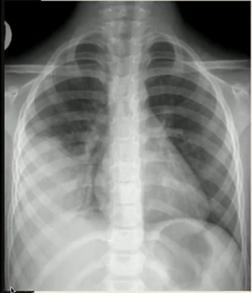

④先天性肺不张/肺发育不良

可分为以下三类:

完全不张:支气管、肺组织均无;

部分不张:支气管盲端,后无肺组织;

发育不良:支气管、肺组织均有,但发育不良(最为常见)。

图24.先天性肺发育不良:(左)左侧无肺组织,肺不张;右侧过度充气,纵隔向患侧偏移;(右)CT可见支气管盲端

先天性肺发育不良可分为原发性和继发性,其中继发性可由胸外挤压(羊水过少)或胸内挤压(先天性膈疝等)原因所致。